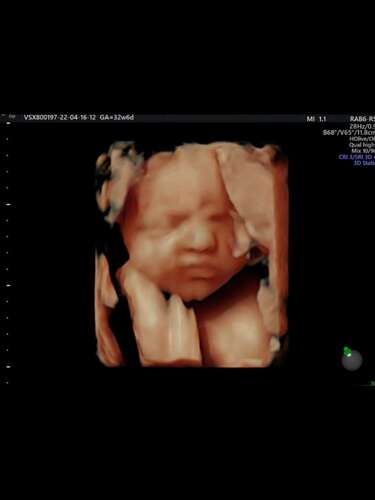

Met de groei echo van 34 weken liet ze even in 3d zien en ik vind dat ze er wel op lijkt

Wat een leuk topic. Wij hebben ook een 3d echo laten maken. En zo te zien lijkt het erg goed! Alleen zijn de echte babies wel veeeel knapper 🥰🥰🥰. Wat een mooie popjes. Gefeliciteerd allemaal mama's 💜